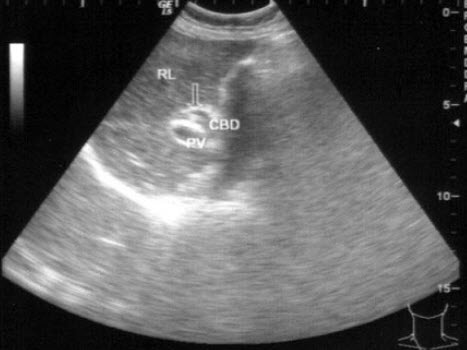

23、单项选择题

患者男46岁,既往有胆囊结石病史,上腹部疼痛不适年余,加重1个月,皮肤、巩膜轻度黄染,B超检查如图所示,根据超声声像图,诊断为()

A.胆囊结石并胆囊炎,肝血管瘤

B.胆囊结石并胆汁淤积,肝血管瘤

C.胆囊结石并胆囊癌,肝转移性癌

D.胆囊结石并肝癌

E.胆囊结石并胆息肉,肝转移性癌